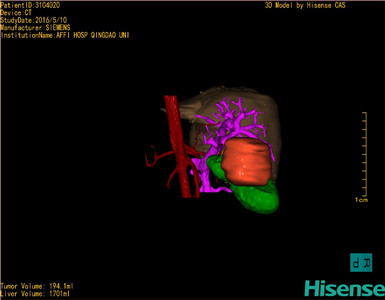

将0.625mm双源薄层CT资料的静脉期和动脉期Dicom格式文件导入海信CAS系统。

通过调节窗宽窗位调整CT序号,对肿瘤,肝实质,胆囊,下腔静脉,肿瘤,肝动脉、门静脉及肝静脉等进行三维重建;系统自动计算肿瘤体积和肝脏体积。

模拟手术操作,自动计算切除肿瘤体积。肝脏体积为1701ml,肿瘤体积为194.1ml,肿瘤体积为肝脏体积的11.4%,通过比对60-70岁正常肝脏体积为1262.7±284.31 ml,通过术前模拟手术,精准判断切除后剩余肝脏体积能耐受,避免肝衰竭发生。

术前手术方案的规划。

术前三维重建:

重建图片